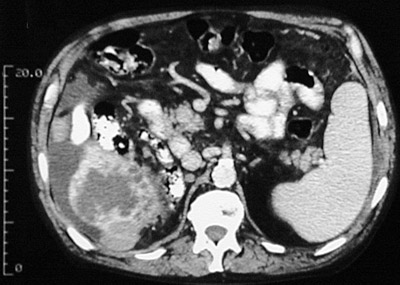

| This abdominal CT scan reveals an hepatocellular carcinoma, with areas of less attenuation from extensive tumor necrosis, involving the inferior margin of the right lobe of the liver. In the view above, this carcinoma has invaded through the liver capsule and extended to the abdominal wall. Note the presence of ascitic fluid as well. Hepatocellular carcinomas that rupture through the liver capsule may also produce a hemoperitoneum. |